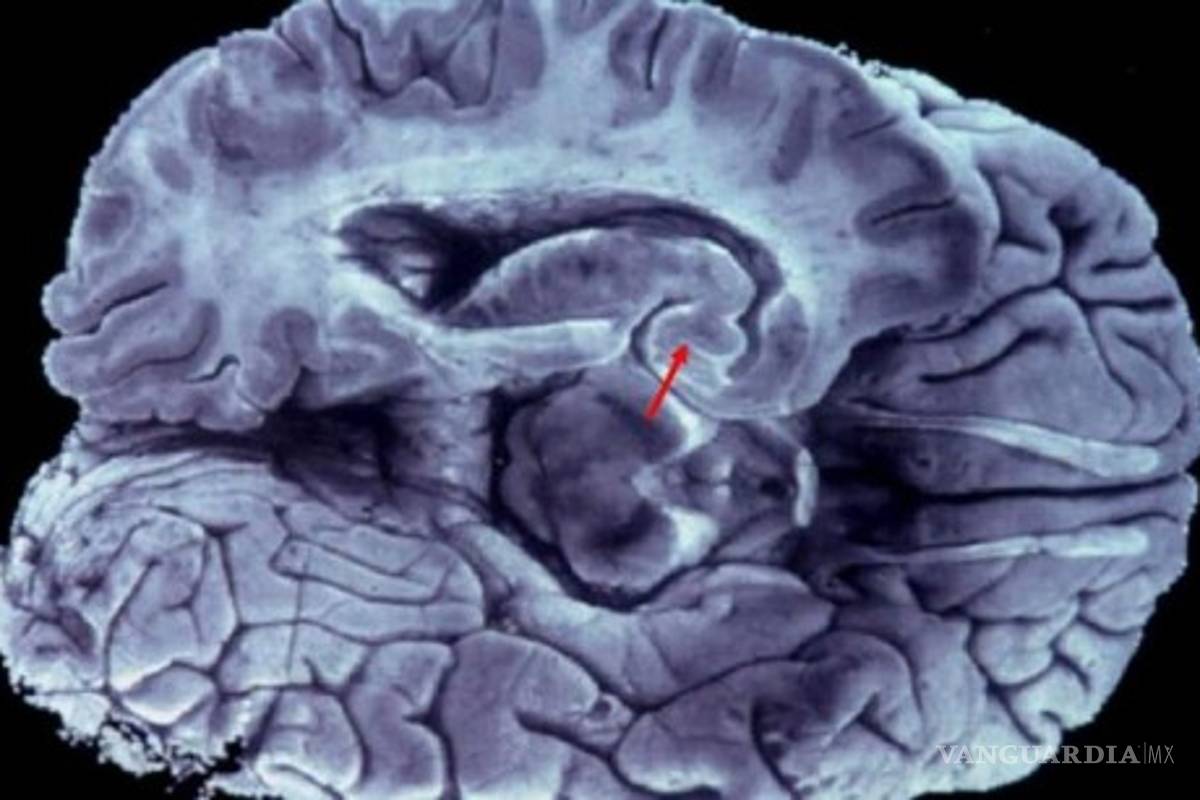

Con el apoyo de las nuevas herramientas, como la resonancia magnética, por ejemplo, es posible medir el volumen de las áreas cerebrales, en particular las involucradas con la memoria y compararlas con las de personas sanas.